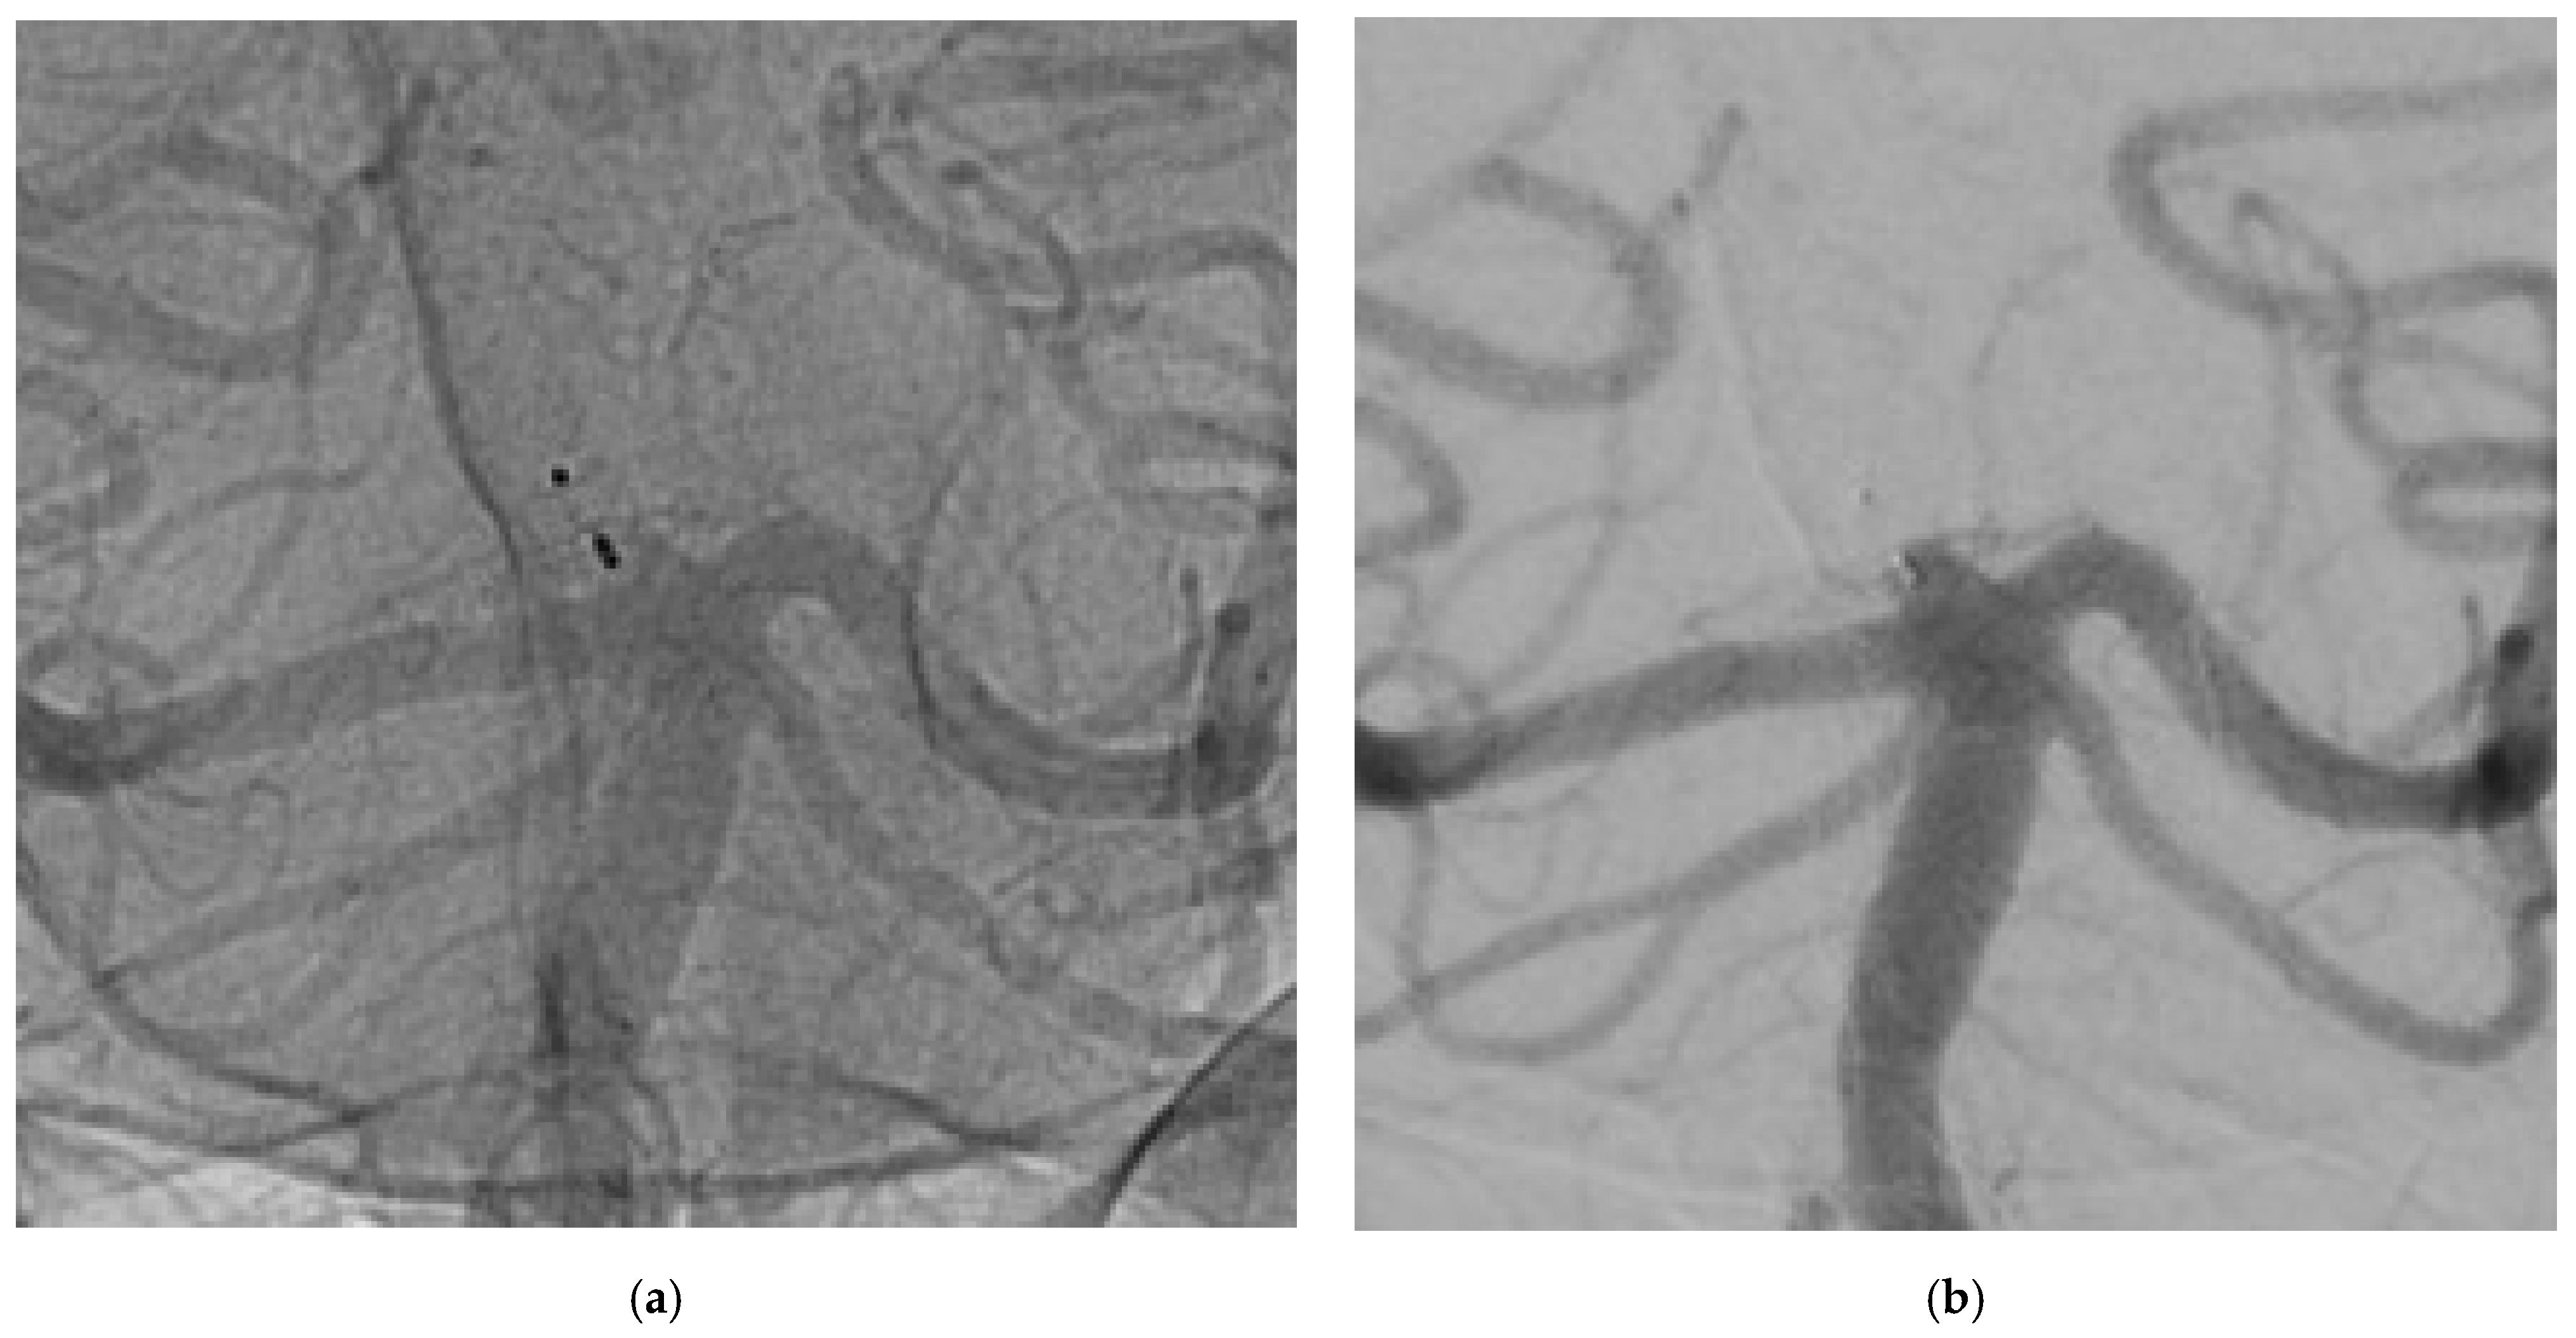

Although incomplete occlusion was identified in 11.1% of cases—slightly higher than what reported by WEBCAST 2—, our findings attest an excellent stability of WEB over time. At both follow-ups, the reperfused neck neither had grown nor had it displayed a minimal increase in size (<2 mm). Hence, retreatment was not required (Figure 1).

Figure 1.

The images show a wide neck aneurysm of the apex of the basilar artery treated using WEB 3 × 2 mm. (a) not-substracted DSA at 3-years, (b) substracted DSA at 3-years. An aneurysm adeguate occlusion was detected and confirmed by 3D protocol.